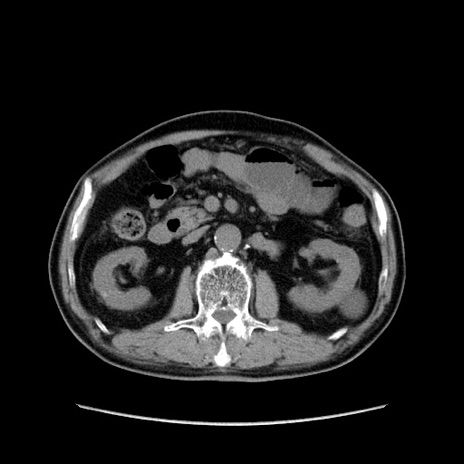

症例24(横断像)

【症例】80歳代男性

【主訴】左側腹部痛、嘔吐

【現病歴】本日早朝より左腹部に痛みあり。昼頃嘔吐認めたため、救急要請。

【既往歴】直腸癌(Mile手術)、胆摘

【身体所見】意識清明、BT 35.9℃、BP 221/93mmHg、SpO2 97%(RA) 、腹部:左ストーマ周囲に限局性の腹部膨隆あり。 膨隆部自発痛・圧痛あり・軟。

【データ】WBC 7700、CRP 0.09